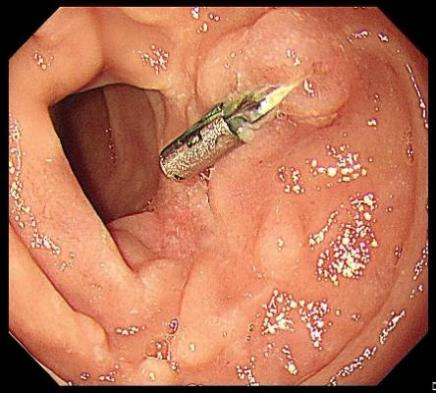

图片

患者女性,47岁,因“黑便”于2023年11月就诊。胃镜检查提示十二指肠存在一直径约2 cm的黏膜下病变,表面伴溃疡,活检病理结果提示为胃肠道间质瘤(图1a),腹部增强CT考虑胃肠道间质瘤(图1b),未见周围脏器侵犯及淋巴结转移表现。经多学科团队评估,并与患者充分沟通内镜与外科手术的利弊后,患者最终选择内镜下切除肿瘤。胡兵团队决定行EFTR手术切除肿瘤(图2):首先进行黏膜下注射生理盐水(图2a),为肿瘤剥离创造操作空间;逐层剥离肿瘤(图2b),病灶已向肠腔外生长(图2c),实施全层切除直至肿瘤完整剥离(图2d),用圈套器取出肿瘤(图2e);采用双层荷包缝合技术,通过尼龙环联合钛夹封闭肠壁缺损(图2f);术毕行腹腔穿刺排气及鼻肠管胃肠减压。术后切除标本大小约4.0 cm×3.0 cm×2.0 cm,病理结果证实为胃肠道间质瘤(低危)且达到R0切除(图3)。术后6个月胃镜检查显示创面愈合良好(图4)。随访20个月,患者未出现内镜手术相关并发症、肿瘤复发或转移。

图1 术前十二指肠检查结果。1a.白光胃镜下显示十二指肠黏膜下病变,表面伴溃疡;1b.CT提示胃肠道间质瘤(黄箭)